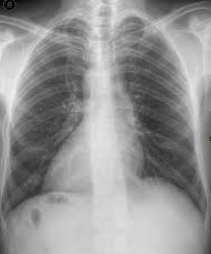

What is Dextrocardia?

A congenital condition where the heart is positioned toward the right side of the thorax instead of the left.